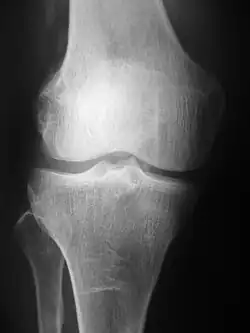

Projection (plain) radiography

Projectional radiograph of the knee

Radiographs (originally called roentgenographs, named after the discoverer of X-rays, Wilhelm Conrad Röntgen) are produced by transmitting X-rays through a patient. The X-rays are projected through the body onto a detector; an image is formed based on which rays pass through (and are detected) versus those that are absorbed or scattered in the patient (and thus are not detected). Röntgen discovered X-rays on November 8, 1895,[5] and received the first Nobel Prize in Physics in 1901 for this discovery.[6] In film-screen radiography, an X-ray tube generates a beam of X-rays, which is aimed at the patient. The X-rays that pass through the patient are filtered through a device called a grid or X-ray filter, to reduce scatter, and strike an undeveloped film, which is held tightly to a screen of light-emitting phosphors in a light-tight cassette. The film is then developed chemically and an image appears on the film. Film-screen radiography is being replaced by phosphor plate radiography but more recently by digital radiography (DR) and the EOS imaging.[7] In the two latest systems, the X-rays strike sensors that converts the signals generated into digital information, which is transmitted and converted into an image displayed on a computer screen. In digital radiography the sensors shape a plate, but in the EOS system, which is a slot-scanning system, a linear sensor vertically scans the patient.

Plain radiography was one of the earliest imaging modalities used in clinical medicine and remained the most widely used for several decades. Due to its broad availability, speed, and relatively low cost, it continues to be a common first-line tool in radiologic evaluation. Despite advances in CT, MRI, and other imaging techniques, there are many conditions in which traditional radiographs remain helpful in diagnosis. These include arthritis, pneumonia, bone tumors, fractures, congenital skeletal anomalies, and certain types of kidney stones.